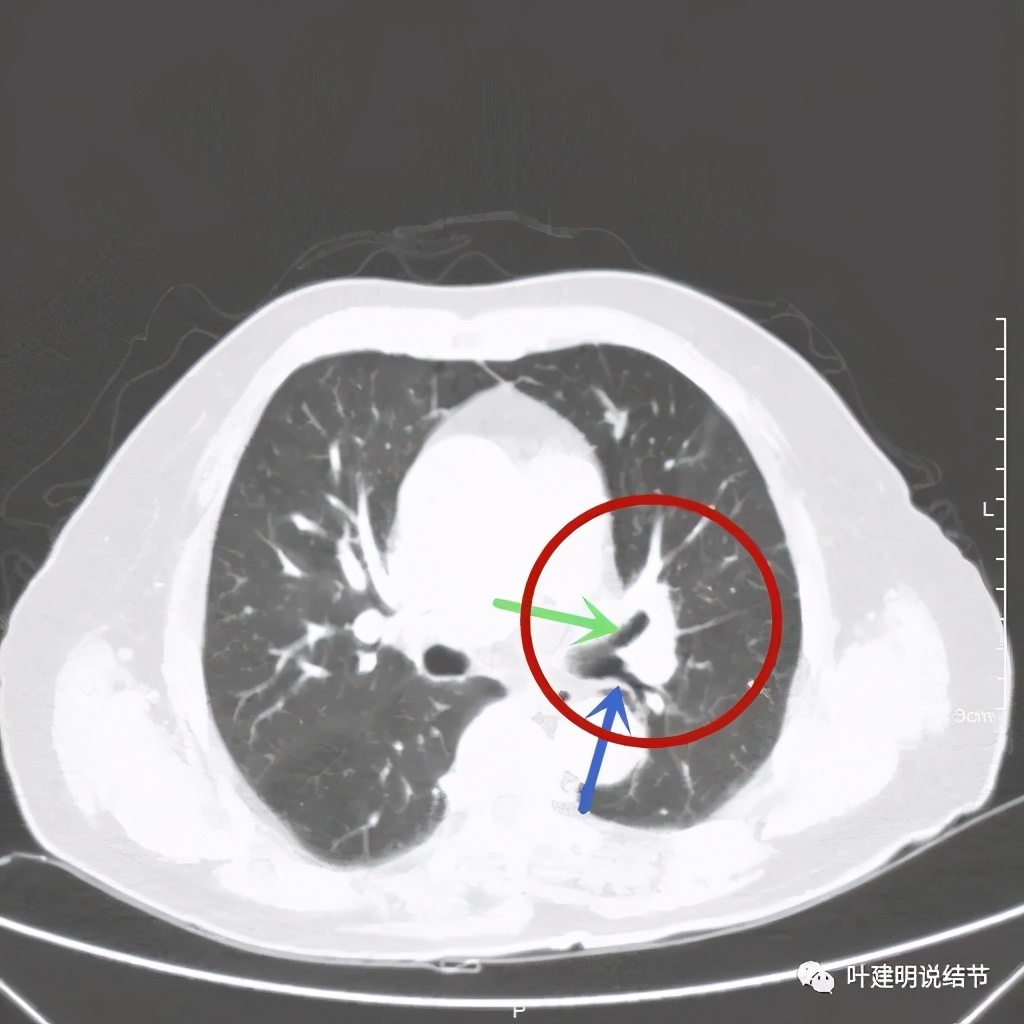

上图桔色箭头示左肺动脉分支处仍被软组织(原肿瘤所在)包绕,粉色箭头示肺动脉仍与肿瘤处关系密切

上图也示桔色箭头示左肺动脉分支处仍被软组织(原肿瘤所在)包绕,粉色箭头示肺动脉仍与肿瘤处关系密切

上图示肿瘤部位仍与肺动脉关系密切,似乎未能脱开,红色示肿瘤处

上图绿色示左上叶支气管,蓝色示下叶支气管开口处